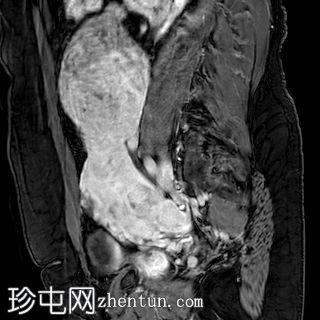

入院时CT检查

CT

腹部中部可见一巨大、不均匀、中心坏死的肿块。

中至大量腹水。

子宫肌瘤。